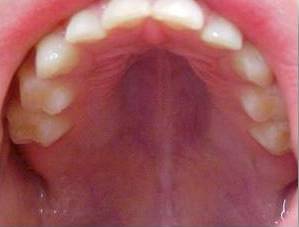

Pela passagem do ar pela boca o palato(céu da boca) sofre uma pressão negativa fazendo com que esse fique fundo e estreito causando uma mordida cruza uni ou bilateral. É comum também encontrar casos de mordida aberta anterior. A colocação de um expansor no céu da boca irá abrir as vias aéreas e passará a respirar normalmente pelo nariz. Constatado o problema de respiração bucal, o tratamento precoce é o mais indicado, especialmente na infância quando os ossos da face e arcada dentária estão em formação e crescimento.

Palato estreito é uma das características do respirador bucal